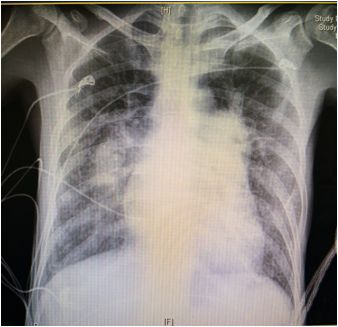

胸部X线

➤ 两肺纹理杂乱

➤ 双肺门动脉扩张,外周肺纹理相对纤细

➤ 双侧肋膈角区未包全

➤ 主动脉结不宽;肺动脉段明显凸出

➤ 右心圆隆